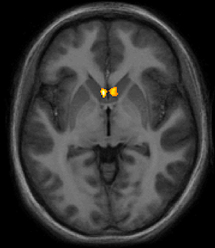

El alivio del dolor inducido por el amor ha sido asociado a la activación en estructuras cerebrales profundas, como el núcleo accumbens (en color en la imagen). Fuente: Universidad de Stanford.

La analgesia inducida por el amor, por el contrario, estuvo más relacionada con las áreas de recompensa del cerebro, con estructuras profundas de éste que pueden bloquear el dolor a un nivel espinal (de la misma forma que lo hacen los analgésicos opiáceos, por ejemplo).

Una de las regiones clave del alivio provocado por el amor fue el llamado núcleo accumbens, un área del cerebro que se cree que tiene un papel importante en la recompensa, la risa, el placer, la adicción y el miedo.

La analgesia inducida por el amor, por el contrario, estuvo más relacionada con las áreas de recompensa del cerebro, con estructuras profundas de éste que pueden bloquear el dolor a un nivel espinal (de la misma forma que lo hacen los analgésicos opiáceos, por ejemplo).

Una de las regiones clave del alivio provocado por el amor fue el llamado núcleo accumbens, un área del cerebro que se cree que tiene un papel importante en la recompensa, la risa, el placer, la adicción y el miedo.